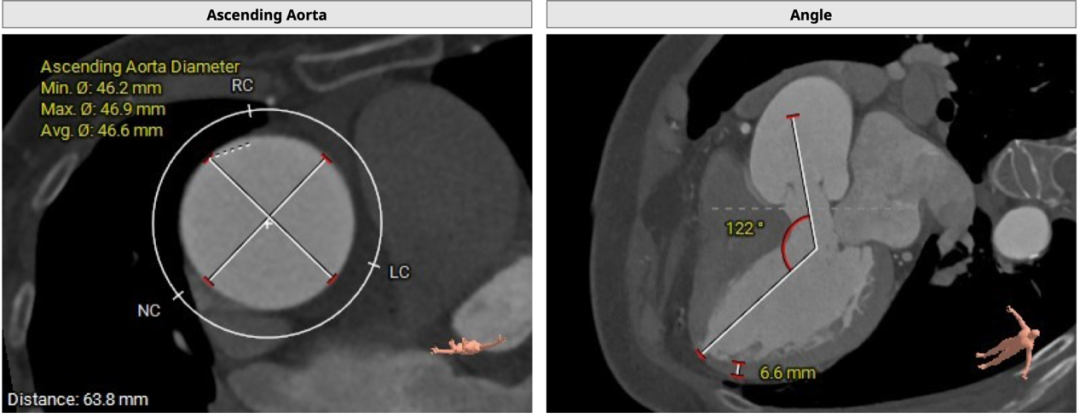

CT分析

双侧冠脉开口高度可LCA:13.9mm,RCA:21.8mm:

横位心: